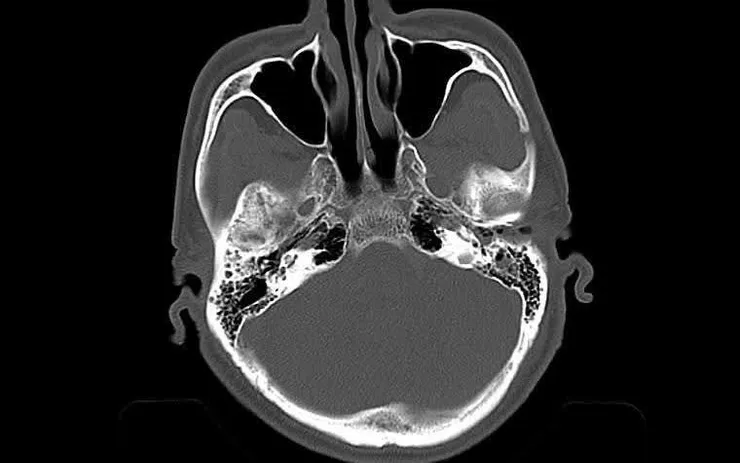

Khi vào Khoa Cấp cứu, bệnh nhân tỉnh nhưng tiếp xúc chậm, sinh hiệu tạm ổn định, có vết thương vùng đỉnh đã được băng ép. Nhận định nguy cơ tổn thương não tiến triển, các bác sĩ chỉ định chụp CT sọ não khẩn cấp. Kết quả cho thấy tụ máu dưới màng cứng hai bán cầu, bên trái dày tới 18 mm; xuất huyết dưới nhện rải rác; đường giữa lệch 15 mm - dấu hiệu chèn ép não nặng, kèm vỡ xương sọ.